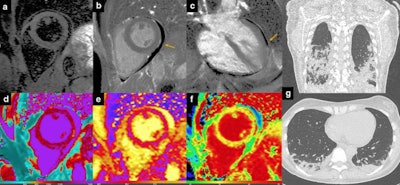

Despite the fact that CT and cardiac MRI are not included in the diagnostic criteria for pericarditis, these imaging modalities can provide supportive findings and are strongly recommended as second-level testing for diagnostic workup of the pathology, according to the authors. The hallmark of cardiac MRI in acute pericarditis includes the combination of diffusely edematous and enhancing pericardial layers with a variable amount of effusion, as shown in the figure below. MRI may serve not only to confirm the diagnosis but also to rule out alternative overlapped diagnoses such as myocarditis or pulmonary embolism.

"What is particularly interesting in this setting is the role of cardiac MR with mapping techniques, which is showing ability to unveil clinically silent myocardial damage consisting of tissue edema, necrosis, and fibrosis, through the measurement of T1 and T2 mapping relaxation times," stated Francone, who is past president of the Italian College of Cardiac Radiology and scientific chair of the European Society of Cardiovascular Radiology.